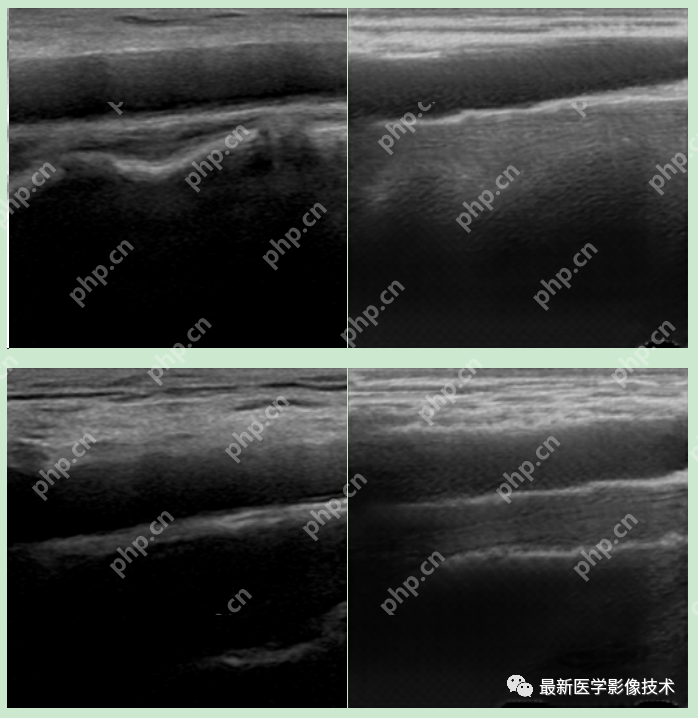

6、测试集部分生成结果

左图为低质量图像,右图为生成的高质量图像。